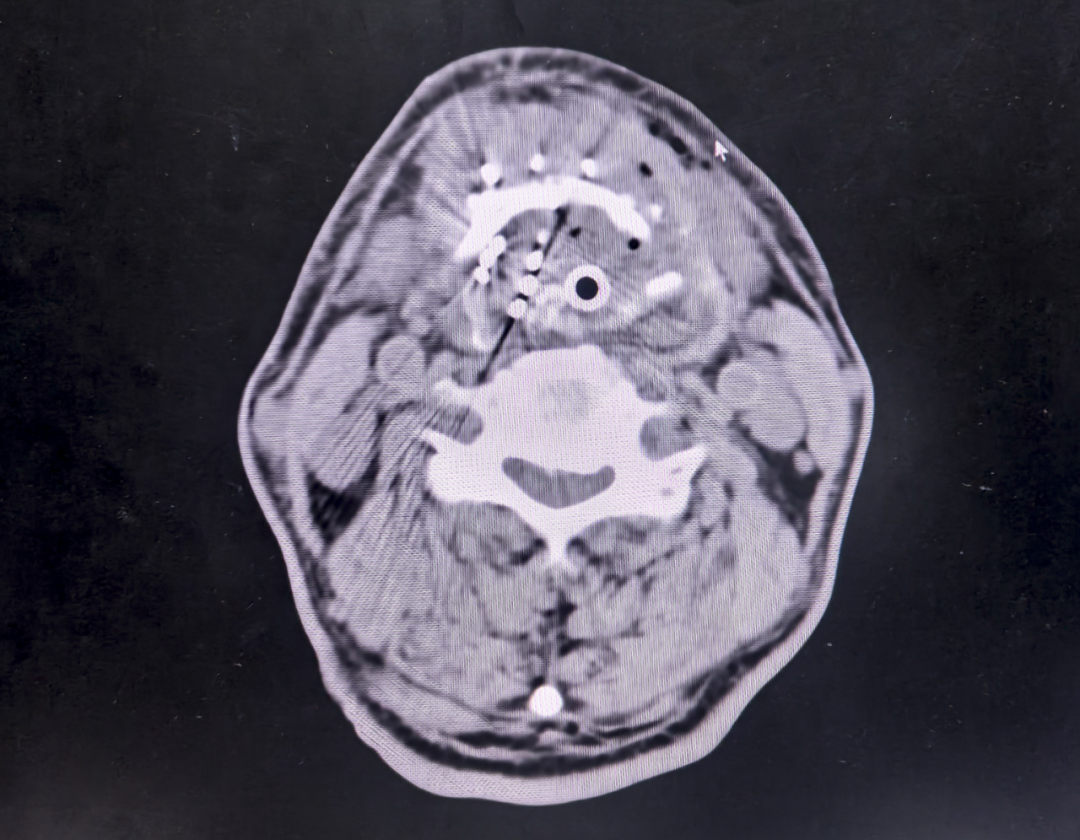

手术全程在CT影像实时导航下进行,11根18G穿刺针以0.5mm精度植入55粒碘125粒子。这种被称为"肿瘤内放疗"的技术,通过持续释放低剂量γ射线,能在保护正常组织的同时对癌细胞进行"定点清除"。

1、三维立体定位:通过TPS(治疗计划系统)预先计算粒子分布,确保辐射剂量覆盖肿瘤又不损伤声带、气管。

2、动态调整机制:术中两次CT扫描比对,及时修正穿刺角度偏差。